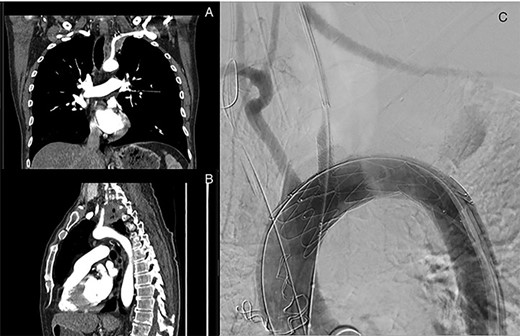

An otherwise healthy 59-year-old-male ex-smoker presented with 6 months of left-sided shoulder pain that radiated down the arm and a 30-pound weight loss. He did not have intrinsic hand muscle weakness or Horner’s syndrome [1]. Physical examination and blood tests were normal. MRI to investigate suspected cervical radiculopathy demonstrated a 4.7-cm left upper lobe apical medial tumour invading the T1-T3 vertebral bodies, T1 nerve root and head of the left second rib. The tumour encased the left subclavian artery near its origin (Fig. 1A and B).

Left superior sulcus tumour encasing the left subclavian artery requiring a left common carotid to subclavian artery bypass and TEVAR placement using in situ fenestration for the left common carotid artery to facilitate resection of the tumour.

The first stage involved a left hemi-clamshell incision with neck extension, osteotomy with first rib resection, left carotid-subclavian bypass with 6-mm Dacron graft and TEVAR placement using in situ fenestration for the left common carotid artery to facilitate resection of the tumour off the aorta (Fig. 1C).